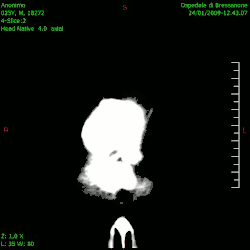

Studio del cranio e dell'encefalo

Lo studio del cranio e dell'encefalo, è uno degli utilizzi più frequenti della tomografia computerizzata, tanto da diventare il gold standard per la diagnosi di molte patologie. La possibilità di ottenere immagini multi-planari ad alta risoluzione e la necessità di visualizzare dettagli spesso propedeutici a un intervento neurochirurgico, diventa indispensabile a causa della complessità di questa regione anatomica, con presenza di numerose strutture sovrapposte. Nonostante la risonanza magnetica stia acquisendo sempre maggiore importanza per quanto riguarda lo studio dell'encefalo, la TC garantisce tempi di esecuzione nettamente inferiori, non presenta problematiche relative alla presenza di forti campi magnetici e di claustrofobia, rendendo tale metodica la prima scelta, nonché la più adatta in situazioni di emergenza come traumi cranici e sospetti ictus cerebrali (emorragici o ischemici).[28]

Per quanto riguarda lo studio dell'encefalo, l'esame consiste in una scansione (con o senza mezzo di contrasto) che comprenda la regione che va dal foro occipitale fino al vertice del cranio, seguendo un orientamento che può basarsi su diversi piani anatomici (generalmente orbito-meatale o neuro-oculare).[29] Lo studio può essere completato da una ricostruzione multi-planare delle immagini ottenute tramite i tre piani spaziali.[30] Solitamente la TC encefalo viene utilizzata per la diagnosi di lesioni cerebrali e cerebellari di varia eziologia, neoplasie, ictus, forme di demenza senile, idrocefali, ecc.[28]